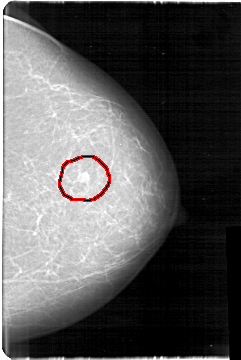

D_4109_1.RIGHT_MLO

FILE: D_4109_1.LEFT_MLO.OVERLAY

TOTAL_ABNORMALITIES 1

ABNORMALITY 1

LESION_TYPE MASS SHAPE OVAL MARGINS OBSCURED

ASSESSMENT 3

SUBTLETY 4

PATHOLOGY MALIGNANT

TOTAL_OUTLINES 1

BOUNDARY